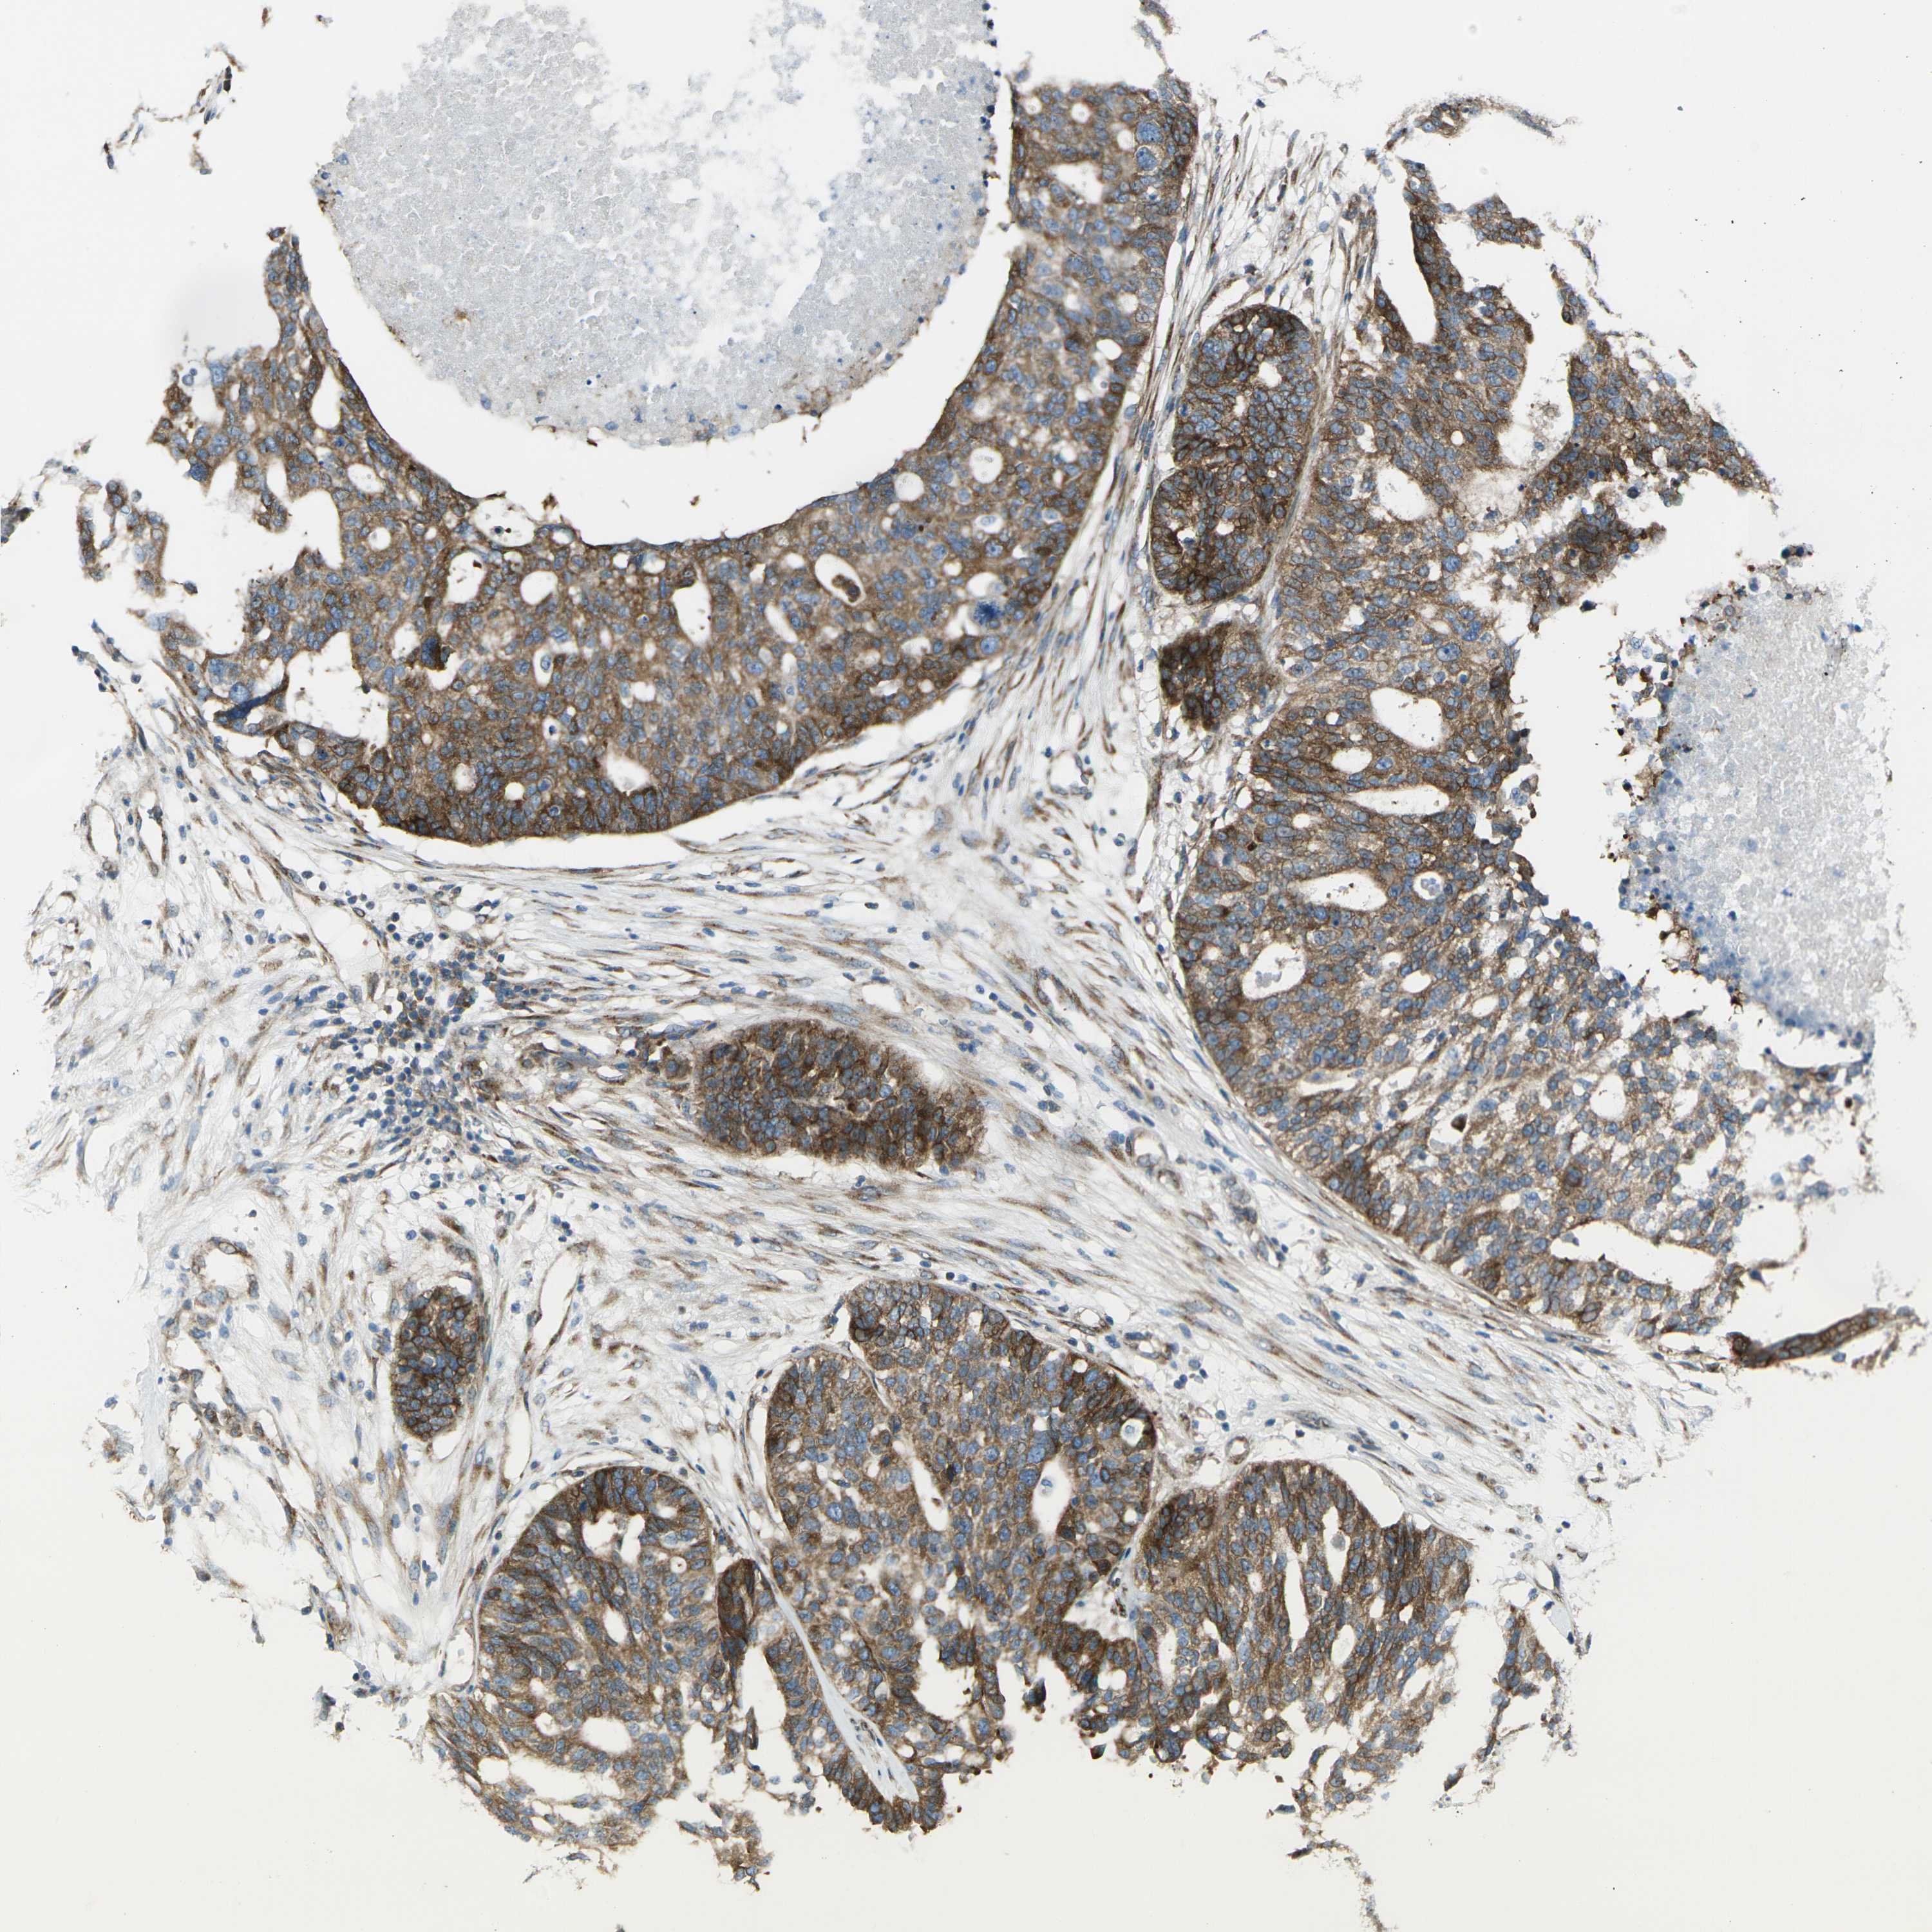

OVARIAN CANCER - Protein expressioni

A mouse-over function shows sample information and annotation data. Click on an image to view it in a full screen mode. Samples can be filtered based on level of antibody staining by selecting one or several of the following categories: high, medium, low and not detected. The assay and annotation is described here.

Note that samples used for immunohistochemistry by the Human Protein Atlas do not correspond to samples in the TCGA dataset.

Antibody stainingi

Antibody staining in the annotated cell types in the current human tissue is reported as not detected, low, medium, or high, based on conventional immunohistochemistry profiling in selected tissues. This score is based on the combination of the staining intensity and fraction of stained cells.

Each image is clickable and will lead to virtual microscopy that enables deeper exploration of all samples and also displays staining intensity scores, fraction scores and subcellular localization as well as patient and tissue information for each sample.

Antibody HPA013952

Staining

High

Medium

Low

Not detected

Intensity

Strong

Moderate

Weak

Negative

Quantity

>75%

75%-25%

<25%

None

Location

Nuclear

Cytoplasmic/membranous

Cytoplasmic/membranous,nuclear

Cystadenocarcinoma, serous, NOS

Carcinoma, endometroid

Cystadenocarcinoma, mucinous, NOS

Carcinoma, NOS